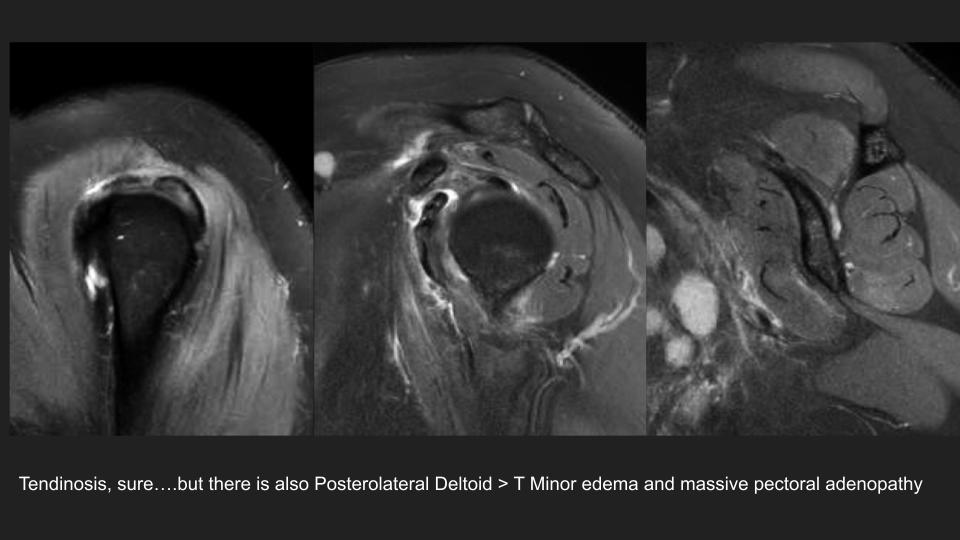

3.jpg